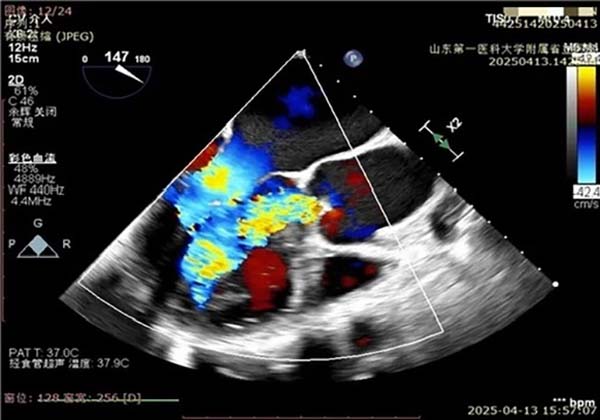

夹子精准定位捕获,二尖瓣返流明显改善

主动脉瓣返流明显增加